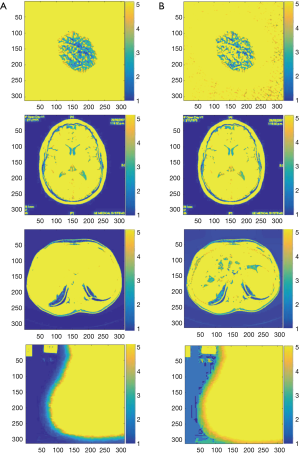

So, for illustrating the quality of image enhancement after applying the proposed optimized method, a simple Fuzzy C-means (FCM) method has been applied to them (75). The results are shown in Figure 10.

As can be seen, using the proposed contrast enhancement not only keep the image details but also improve the image segmentation quality in some cases, especially in liver tumor image.